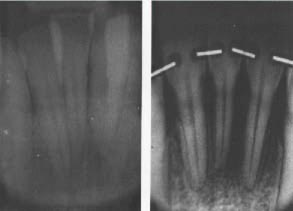

Fig. 8 Case 7. Periapical x-rays before uprighting (left) showing infrabony pocket and proximity of roots of left central and lateral; after two months (center) showing improvement; and after four months (right) left central is uprighted and roots of left central and lateral are separated.

Fig. 9 Case 7. A. before treatment. B. With upper and lower removable appliances in place. Note posterior bite plane on lower appliance to restore lost vertical dimension. C. After orthodontic treatment, periodontic treatment, and temporary stabilization. Elimination of deep pocket has resulted in lengthening of clinical crown of upper left central. D. Completed case after prosthetic restoration.